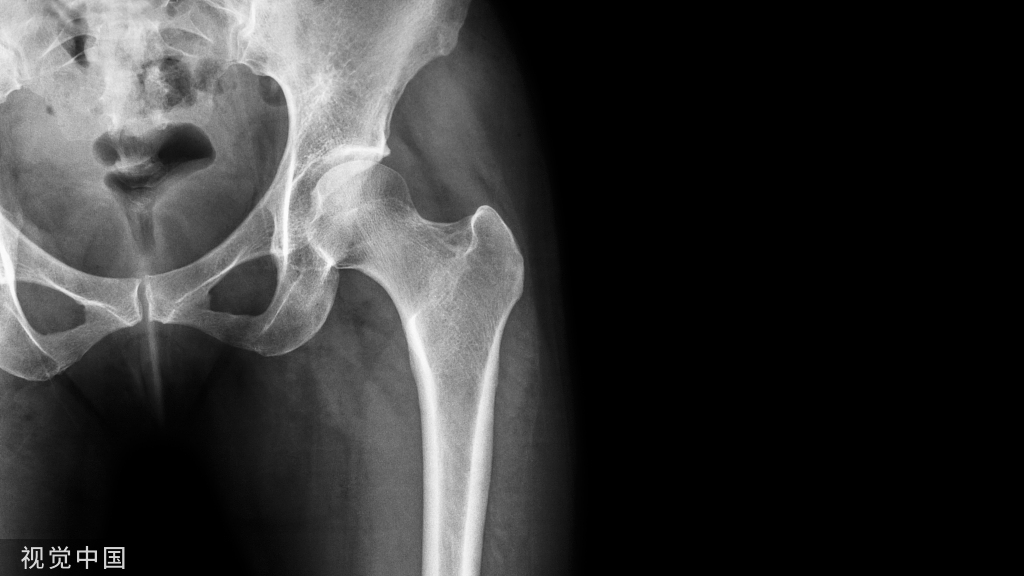

摔倒或车祸后髋部疼痛的患者急诊经常可见,临床医生会常规给他们行影像学检查如骨盆前后位、髋关节正侧位 X 线片等,明确是否存在骨折。

对于这类患者的 X 线片,需仔细观察:① 双侧股骨头及关节间隙的对称性② 髋臼及泪滴的完整性③ 4 个重要骨性标志的连续性:代表前柱的髂耻线、代表后柱的髂坐线、髋臼前缘和髋臼后缘

尽管仔细检查和评估,仍有一些外伤后髋部疼痛的患者,存在 X 片上难以发现的隐匿性髋部骨折。这种情况下,可以选择对骨髓水肿高度敏感的 MRI 进行随访(图 1)。

图 1 长跑运动员股骨隐匿性、应力性骨折。A 为髋部正位 片,虽未见明显骨折,但股骨颈基底部可见一模糊的线性硬化带(箭头)B 为 MRI 冠状位 STIR 序列扫描,示股骨颈应力侧可见一线性低密度信号影,周围包绕骨髓水肿的高密度影

从这个案例来看,长期运动的患者,如果出现髋部疼痛,X 线即使无特殊表现,也应考虑应力性骨折的可能性。

股骨近端骨折

股骨颈骨折常发生在老年人,头下型骨折最常见,但是当股骨外旋或有明显的关节炎骨赘形成时,骨折较难发现。此外,肥胖和骨量减少增加髋部 X 片诊断难度,所以需格外注意。

因骨结构重叠影响,股骨转子骨折发生轻度移位时亦很难发现,加做一个不同角度的 X 线片有助于诊断(图 7)。